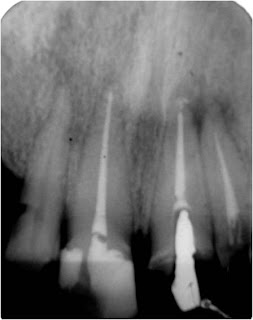

Remoção de Coroa e Núcleo do dente 11 e retratamento em Sessão Única